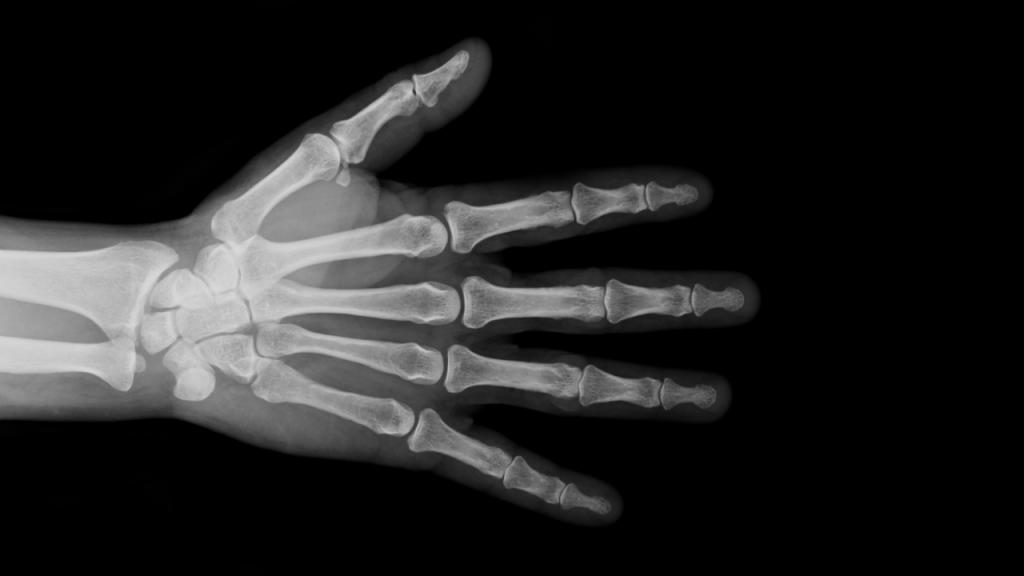

Para comprender el valor de la inteligencia artificial en este contexto, es necesario recordar cómo se ha evaluado históricamente la maduración infantil. Durante décadas, los médicos se han basado en el análisis de radiografías de la mano izquierda. Esta parte del cuerpo, rica en huesos y centros de crecimiento, ofrece una imagen muy representativa de la madurez biológica de un menor.

¿Por qué la mano izquierda? Es una convención establecida para unificar los criterios de evaluación. Lo importante es que en esta mano se puede observar, con claridad, cómo avanza la osificación de los huesos, un proceso que indica en qué fase de desarrollo está una persona joven.

Este método se perfeccionó en el siglo XX gracias al trabajo de investigadores como Todd y sus discípulos Greulich y Pyle, quienes elaboraron en 1959 un atlas de radiografías canónicas clasificadas por edad y sexo. Su objetivo era proporcionar una guía visual y accesible para que los evaluadores pudieran comparar la mano izquierda de un paciente y estimar su “edad ósea”, obteniendo así una medida cuantitativa de la maduración biológica.